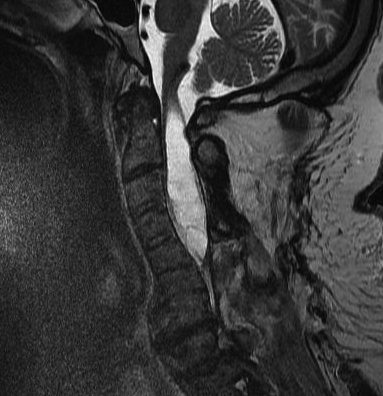

Arnoldi-Chiari Malformation

Congenital abnormality of Cerebellar Tonsils

- herniation of medullary tonsils through foramen magnum into cervical canal

- block CSF flow through foramen Lushka & Malgagne blocked

- often need AV shunt

MRI

Most sensitive investigation

- main differential is oedema

- need T1 image

Look for obstructions

- ACM

- spinal cord tumours